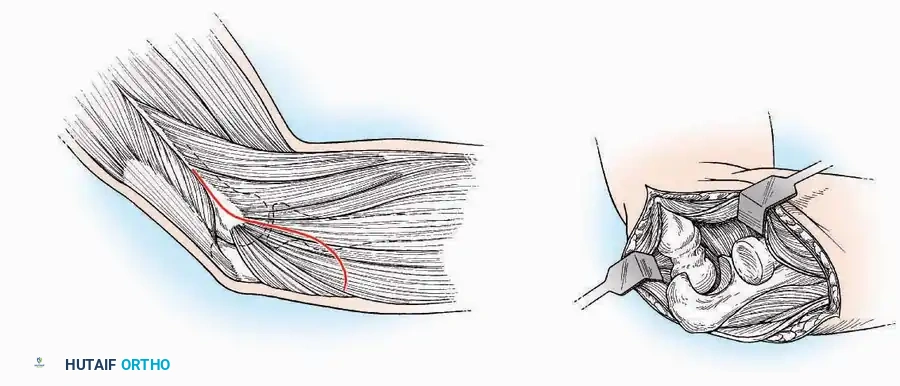

Lateral Approach (Extensile Lateral)

This is the workhorse approach for open reduction and internal fixation (ORIF) of displaced intra-articular calcaneal fractures.

Indications: ORIF of calcaneus fractures, lateral wall exostectomy, subtalar arthrodesis.

Positioning: Lateral decubitus with the operative leg up, or supine with a large bump under the ipsilateral hip to internally rotate the leg.

Surgical Technique:

* Incision: Begin the incision on the lateral margin of the Achilles tendon near its insertion. Extend it distally to a point 4 cm inferior and 2.5 cm anterior to the lateral malleolus. (For trauma, a classic L-shaped extensile incision is often used, dropping straight down anterior to the Achilles, then curving gently toward the base of the 5th metatarsal).

* Superficial Dissection: Divide the superficial and deep fasciae. It is imperative to create a "full-thickness" flap containing skin, subcutaneous fat, and periosteum to prevent flap necrosis.

* Nerve Protection: The sural nerve crosses the proximal and distal limbs of this approach. It must be identified and protected within the anterior flap.

* Deep Dissection: Isolate the peroneal tendons (longus and brevis). Incise and elevate the periosteum below the tendons to expose the lateral wall of the calcaneus.

* Tendon Management: If severe deformity or infection is present, the peroneal tendons may be divided via Z-plasty and repaired at the conclusion of the case, though this is rarely necessary in modern fracture care.

Medial Approach

Indications: Fixation of sustentaculum tali fractures, medial process fractures, or excision of medial tarsal coalitions.

Positioning: Supine with the hip externally rotated and knee flexed (figure-of-four position).

Surgical Technique:

* Incision: Begin 2.5 cm anterior and 4 cm inferior to the medial malleolus. Carry it posteriorly along the medial surface of the foot toward the Achilles tendon.

* Superficial Dissection: Divide the fat and fascia to define the inferior margin of the abductor hallucis muscle.

* Deep Dissection: Mobilize the abductor hallucis muscle belly and retract it dorsally to expose the medial and inferomedial aspects of the calcaneal body.

* Plantar Exposure: Continue distally by dividing the plantar aponeurosis and the muscular attachments to the calcaneus, or strip them subperiosteally with an osteotome.

* Neurovascular Warning: Meticulously identify and protect the medial calcaneal nerve and the nerve to the abductor digiti minimi (first branch of the lateral plantar nerve), which are highly vulnerable during inferior retraction.